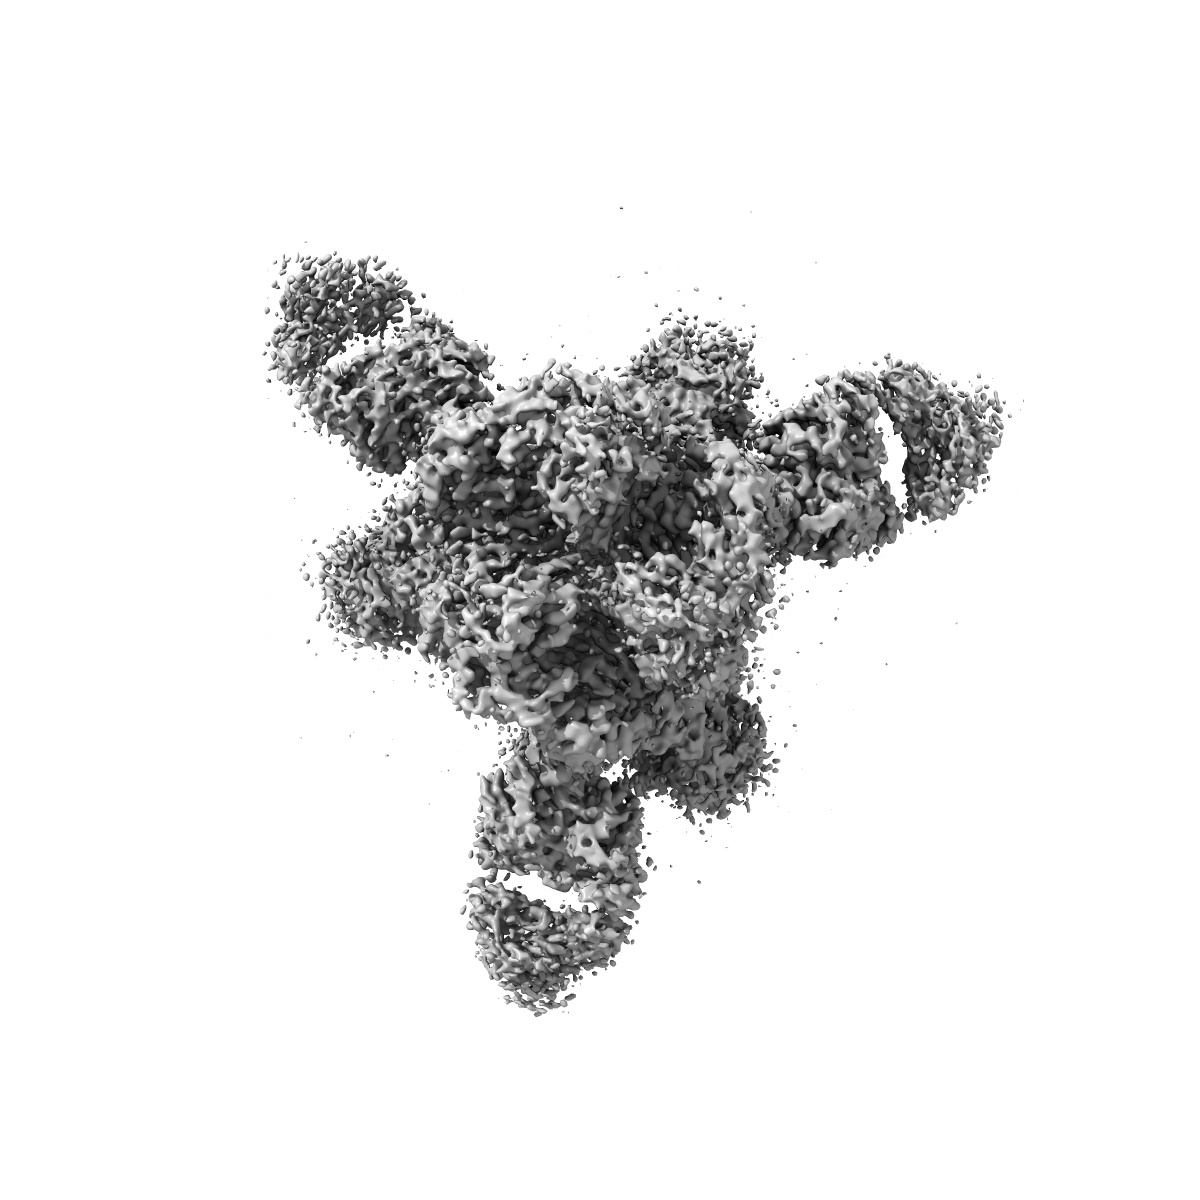

Cryo-EM structure of SARS-CoV-2 Delta Spike protein in complex with BA7208 and BA7125 fab

Single-particle3.08 Å

Sample: Cryo-EM structure of SARS-CoV-2 Delta Spike protein in complex with BA7208 and BA7125 fab